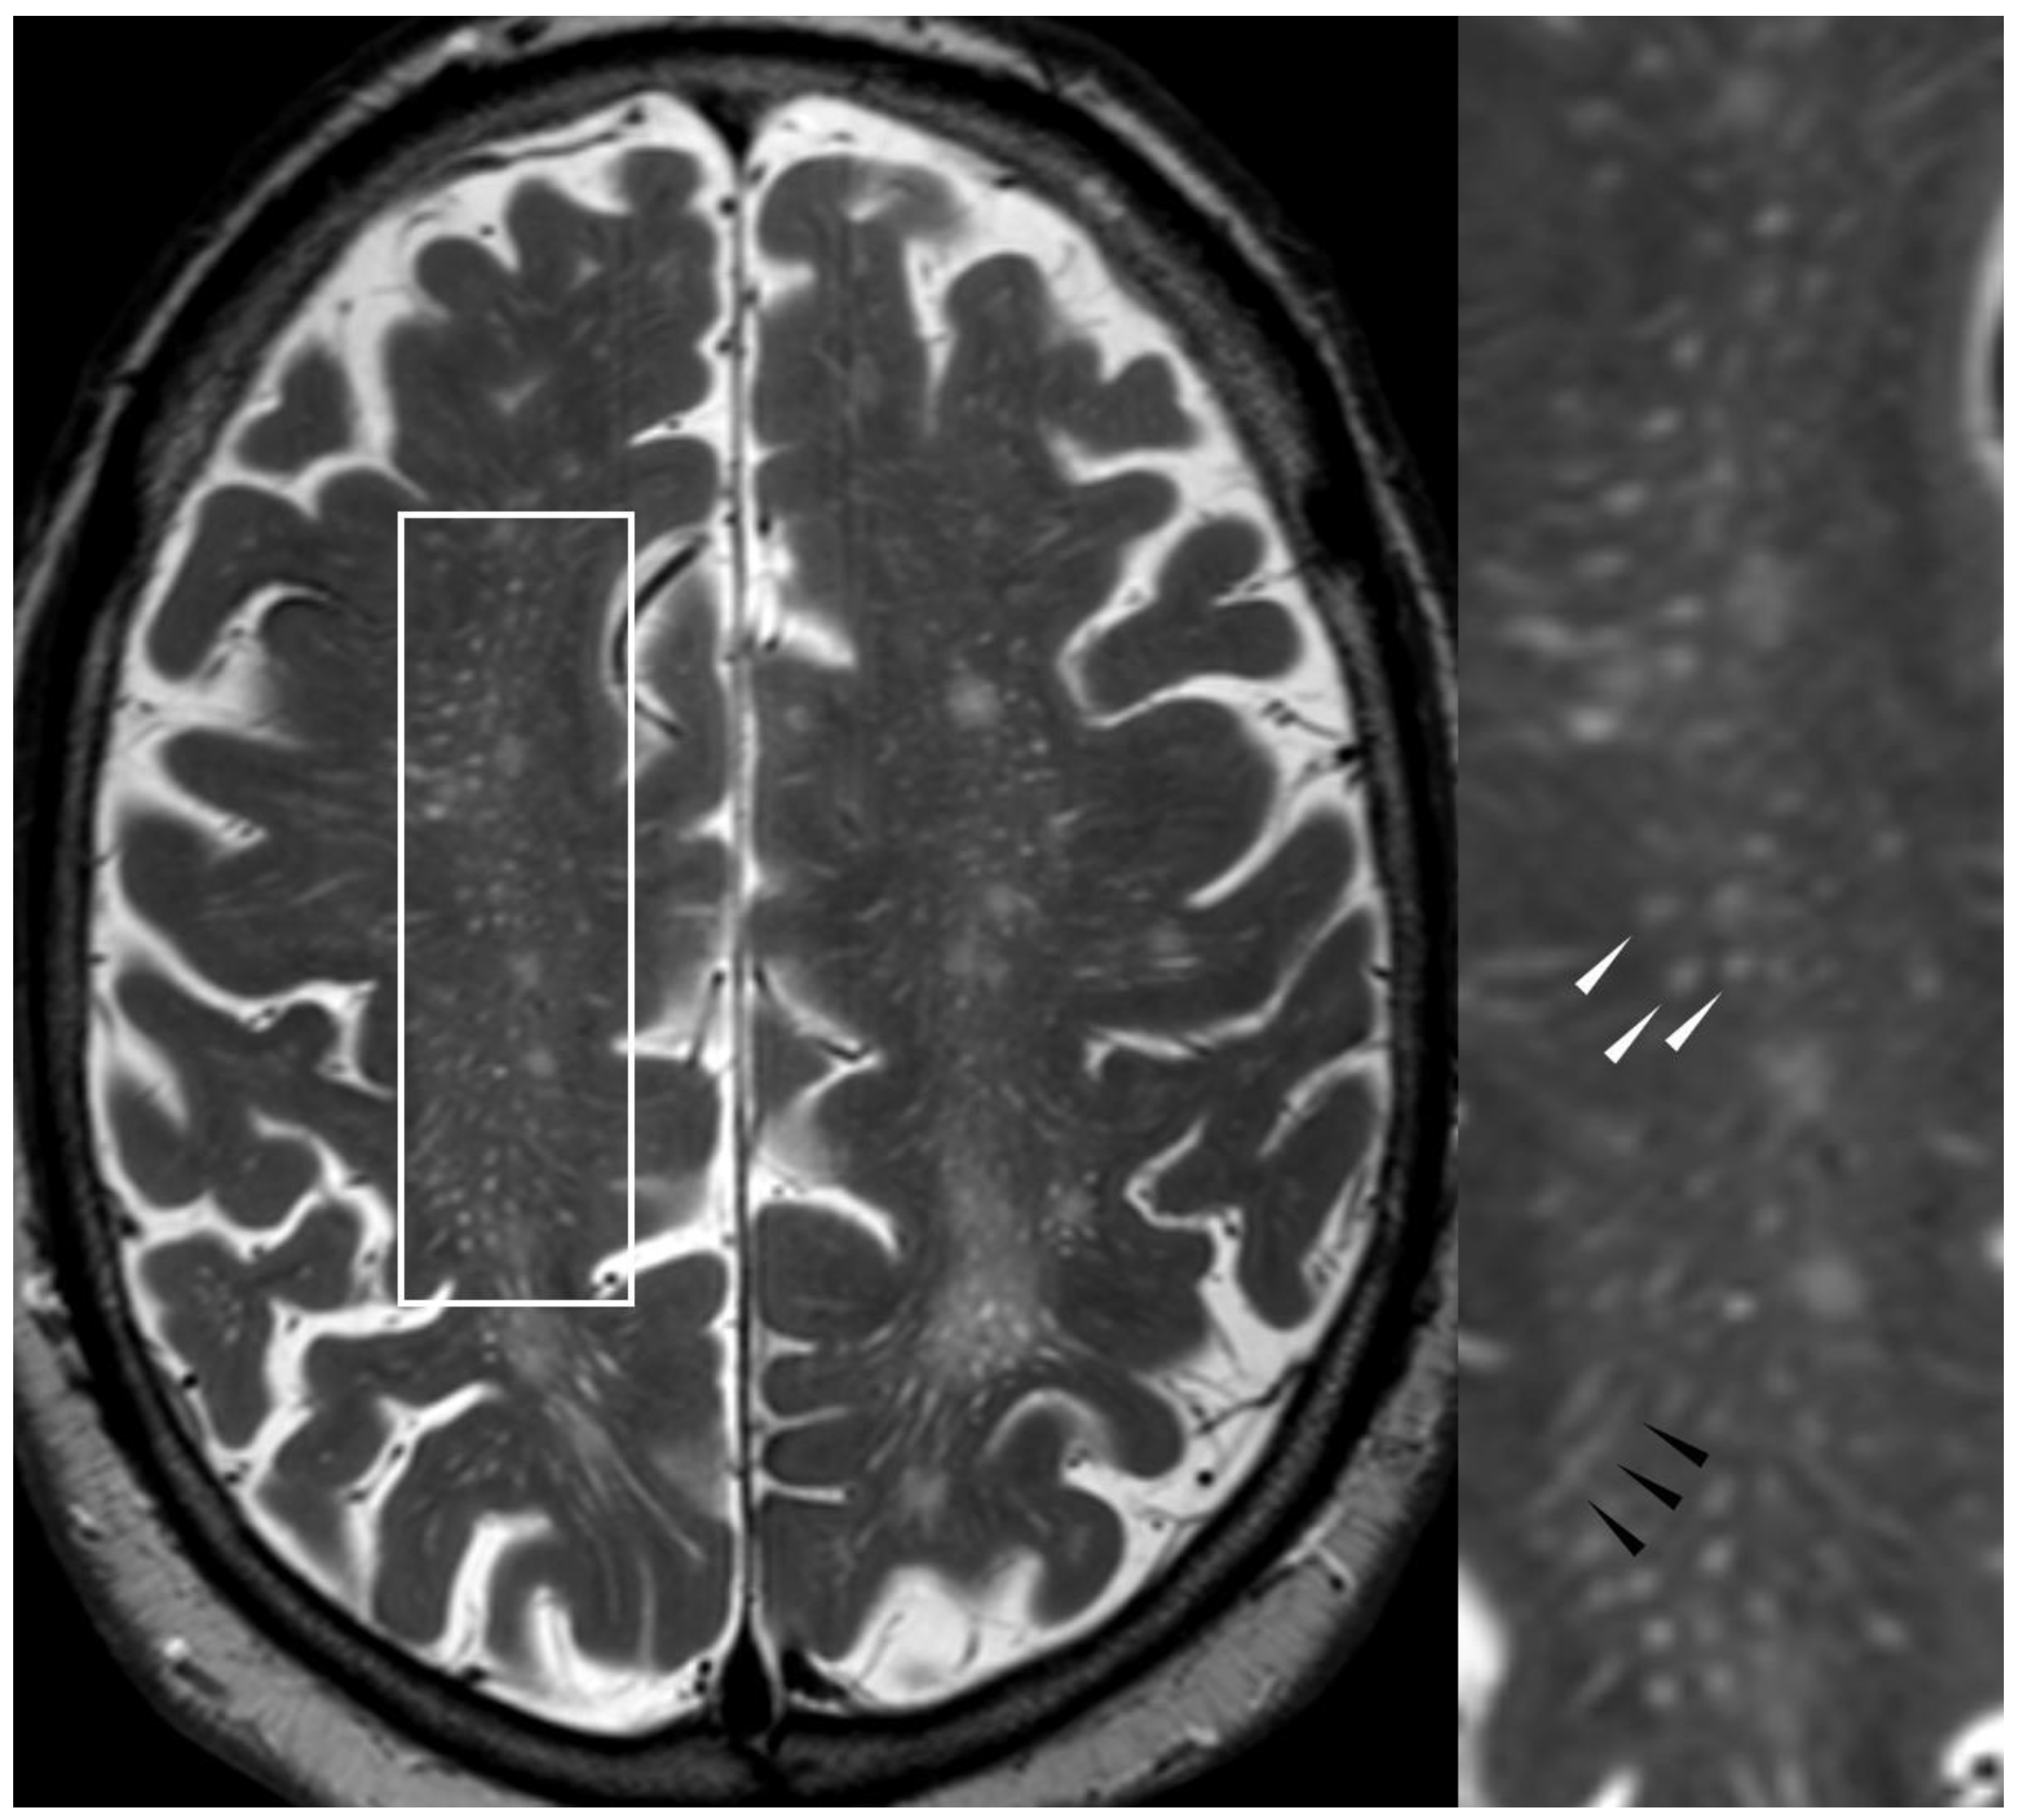

5.2.1. Enlarged Perivascular Spaces

- Charidimou, A.; Boulouis, G.; Pasi, M.; Auriel, E.; van Etten, E.S.; Haley, K.; Ayres, A.; Schwab, K.M.; Martinez-Ramirez, S.; Goldstein, J.N.; et al. MRI-visible perivascular spaces in cerebral amyloid angiopathy and hypertensive arteriopathy. Neurology 2017, 88, 1157–1164. [Google Scholar] [CrossRef] [PubMed]